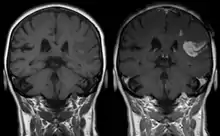

Le gadolinium (sous forme chélatée ou libre) est retenu dans le cerveau, en particulier dans le noyau dentelé et le globus pallidus[11], dès une injection d'un agent de contraste à base de gadolinium (GBCA) (en quantité plus importante pour les linéaires)[12]. Le système glymphatique pourrait être la voie d'accès principale des GBCA au cerveau en intraveineuse[13]. Des études in vitro ont trouvé les agents linéaires (chélateurs moins stables) plus neurotoxiques que ceux macrocycliques[14],[15]. Une étude a trouvé qu'un rehaussement du signal T1 sans administration de contraste (indicateur de la présence de gadolinium) sur les IRM cérébraux d'individus ayant reçu une ou plusieurs injections d'agents linéaires et macrocycliques corrélaient significativement avec une fluence verbale moindre[16]. La confusion est une possible conséquence clinique reportée par plusieurs études[14].